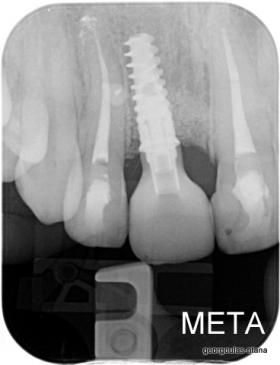

ΑΠΟΚΑΤΑΣΤΑΣΗ ΑΝΩ ΚΕΝΤΡΙΚΟΥ ΤΟΜΕΑ ΜΕ ΜΟΝΗΡΕΣ ΕΜΦΥΤΕΥΜΑ

Η κοπέλα αυτή ήρθε στο ιατρείο με κάταγμα στον δεξιό άνω κεντρικό τομέα. Το δόντι είχε απονευρωθεί στο παρελθόν και είχε αποκατασταθεί με βιδωτό άξονα κ ανασύσταση με ρητίνη και το αισθητικό αποτέλεσμα ήταν φτωχό. Η ασθενής ήθελε να είναι καλυμμένη αισθητικά για όσο χρονικό διάστημα θα διαρκούσε η θεραπεία. Πραγματοποιήθηκε τομογραφία κωνικής δέσμης (CBCT) στην περιοχή και αποφασίστηκε να γίνει εξαγωγή του δοντιού, διατήρηση του όγκου του φατνίου και 3 μήνες μετά τοποθέτηση εμφυτεύματος με ταυτόχρονη χρήση μοσχευμάτων σκληρών κ μαλακών ιστών  για βέλτιστο αισθητικό αποτέλεσμα. Το εμφύτευμα αποκαταστάθηκε με υβριδικό κολόβωμα από διπυριτικό λίθιο και ολοκεραμική στεφάνη από διπυριτικό λίθιο (Emax). Καθ’ όλη τη διάρκεια της θεραπείας, η ασθενής ήταν καλυμμένη αισθητικά με γέφυρα Meryland  συγκολλημένη στα δύο διπλανά δόντια. Μετά την οστεοενσώματωση του εμφυτεύματος και πριν την τελική αποκατάσταση, τοποθετήθηκε στο εμφύτευμα προσωρινή εργασία με σκοπό τη βελτίωση των ούλων.